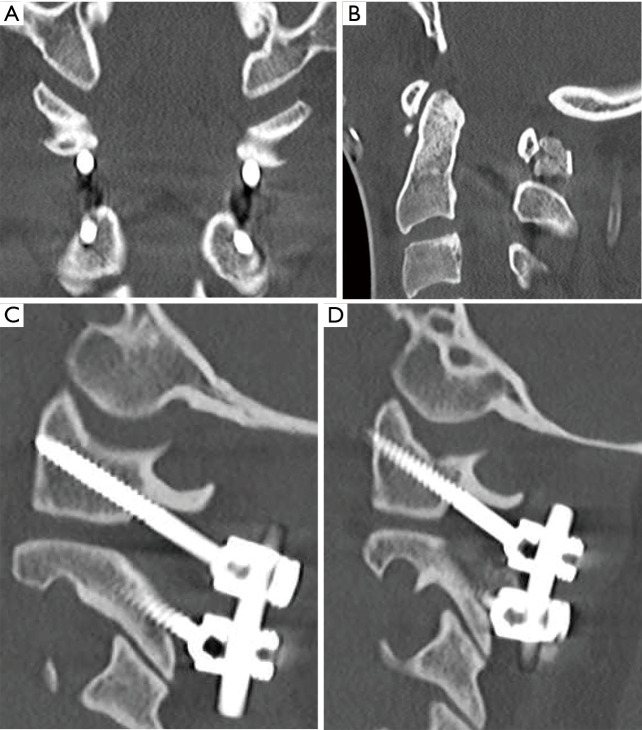

Less than 24 hours after presentation, the patient was taken to the OR for urgent management of his multiple injuries. He first underwent external fixation of his right pilon fracture, followed by C1-C2 posterior instrumentation and fusion (Figure 2). He was placed in a C-collar and transferred to the intensive care unit (ICU) post-operatively. Per our institution protocol, post-operative cervical spine CT was obtained which revealed further distraction and subluxation of the occipitocervical junction bilaterally, with a CCI of 4 mm bilaterally, a basion-dens interval (BDI) of 10 mm, and a Power’s Ratio of 1.1 (Figure 3). Due to concern for significant injury, the patient was brought back urgently to the OR for traction testing to rule out OCD.

Figure 3.

Post-operative CT C-spine revealing (A) coronal view showing distraction of bilateral O-C1 joints, (B) sagittal view showing increased BDI, (C) sagittal view showing right O-C1 joint distraction, (D) sagittal view showing left O-C1 joint distraction. CT, computed tomography; O-C1, atlanto-occipital; BDI, basion-dens interval.